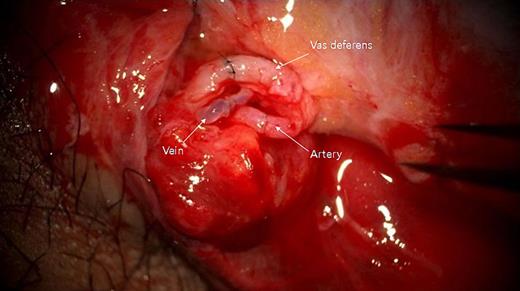

Cooperative surgery was performed by surgeons from the urology and plastic surgery departments. The patient was placed supine in a frog-leg position. The proximal gonadal artery in the spermatic cord was detected easily with pulsating bleeding and secured by clamping without causing vessel injury (Fig. 2). The vas deferens was also found near the gonadal artery with a resilient tactile sense. Thin lumens around the gonadal artery were identified as gonadal veins. The amputated testis was also checked, and the vas deferens was continued from the tail of the epididymis. The gonadal artery was located in the same direction as the vas deferens. The testis was fixed on the scrotal wall to prevent it from roaming freely. The gonadal artery was first connected using 11-0 nylon under an operating microscope (KINEVO 900, Zeiss; Fig. 3). After vein drainage was confirmed, gonadal vein anastomosis was performed with 11-0 nylon (Fig. 3). Lastly, two-layer vasovasostomy was carried out with 8-0 nylon (Fig. 3). After the end-to-end anastomosis of the artery, vein, and vas deferens, the viability of the testis could be confirmed in terms of vascularity on gross and indocyanine green fluorescence perfusion (Fig. 4). The cremasteric muscle of the spermatic cord was reinforced to reduce tension in the anastomosis sites, and orchiopexy was performed to prevent testicular torsion. The other testis was replanted in the same maneuver (right testis: artery 1ea, vein 1ea; left testis: artery 1ea, vein 2ea). The ischemic time of each testis was 7 h (right) and 8.5 h (left). Each testis was raised on a high scrotal area and fixed with the approximated dartos fascia because of the large skin defect of the scrotum (Fig. 5). Lastly, the amputated scrotal wall after defatting was used to cover the whole defect.